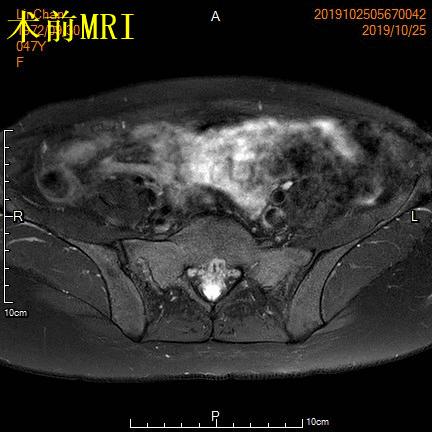

- 术前MRI显示子宫明显增大,病灶主要位于子宫前壁

术前MRI显示子宫明显增大,病灶主要位于子宫前壁

- 术前MRI检查显示子宫明显增大。

术前MRI检查显示子宫明显增大